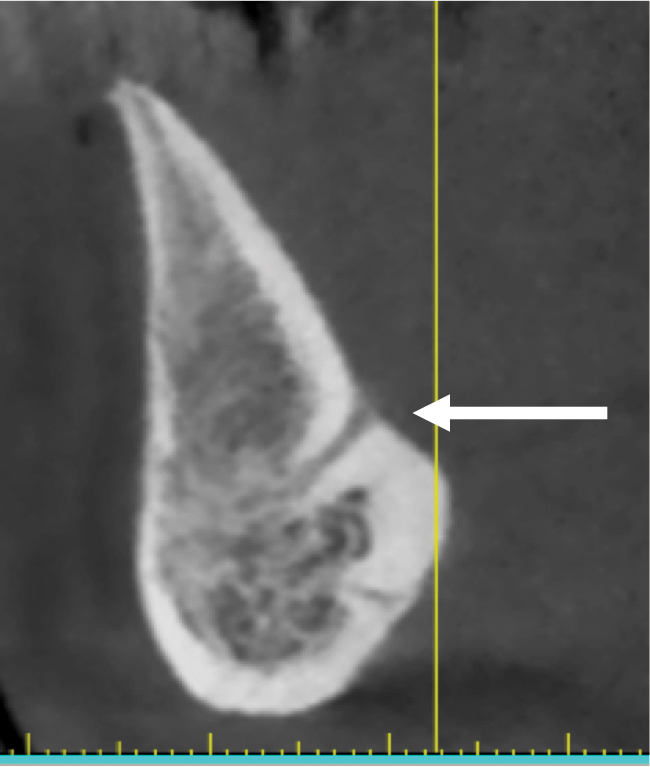

Fig 8. Deficient ridge contour at the osseous crest: cross-sectional view. This ridge (arrow) is not wide enough to receive an implant unless additional bone grafting is done to accommodate the implant’s width or the bone is reduced to a widened part of the ridge suitable for implant insertion.

Figure 8